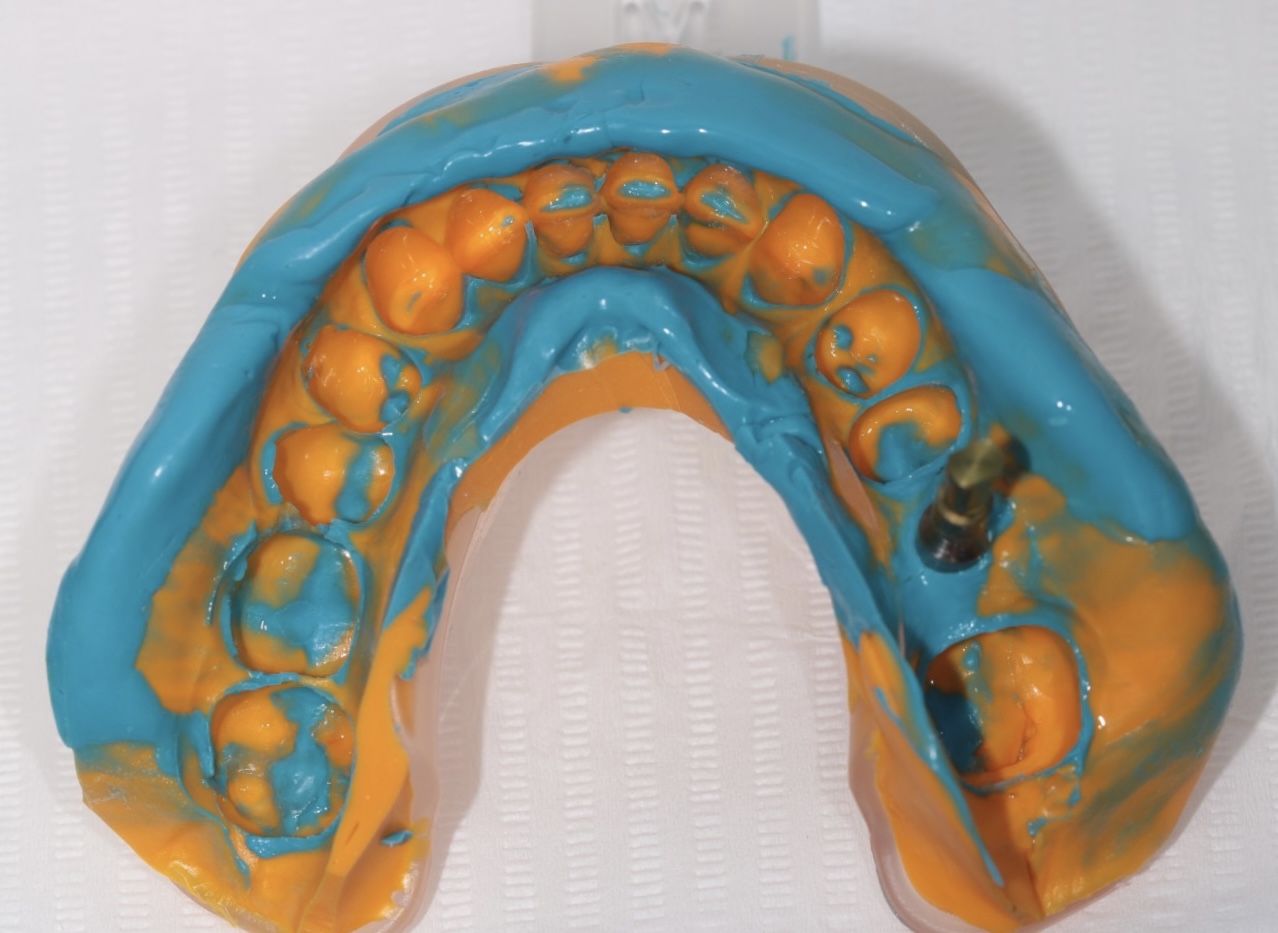

Implantati mogu da budu terapijsko rešenje u različitim situacijama - od nadoknađivanja pojedinačnih zuba u estetski najzahtevnijoj regiji kao što su prednji deo gornje vilice, preko nedostatka vićeg broja zuba pa do full mouth rekonstrukcija, gde se nadoknađuju puni zubni nizovi bilo u jednoj ili u obe vilice ALL-ON-4 ili ALL-ON-6 konceptom.

Naš tim je dovoljno iskusan i stručan za iznalaženje svih ovih rešenja pri čemu se vodimo modernim planiranjem gde željeni oblik i položaj buduće nadoknade diktira položaj implanta, što je imperativ u modernoj implantologiji.

Nekada je ugradnja implanata jednostavna, a nekada je kompleksna i zahteva dodatne hiruške procedure različitog nivoa složenosti da bi se dobili optimalni uslovi za hirurgiju. Naš tim ima znanja, veštine i tehničke mogućnosti za izvođenje svih tih procedura gde se koriste zamenici za kost (“veštačka kost”), kost samog pacijenta, razne vrste membrana (veštačkih ili dobijenih iz krvi samog pacijenta), kao i primena faktora rasta izdvojenih iz krvi sve u cilju dobijanja najboljih uslova za ugradnju implanata i za kasnije protetsko zbrinjavanje kada se pacijent estetski i funkcionalno rehabilituje.